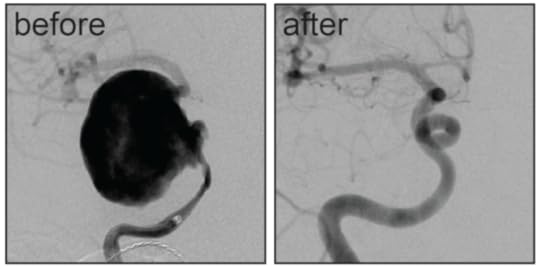

The treatment of brain aneurysms is aimed at disrupting blood flow into the aneurysm. This was traditionally done from the outside by pinching the aneurysm with a metal “clip” or from the inside by filling an aneurysm with metal “coils.” These treatments, however, were not uniformly successful or even possible with some aneurysms. This prompted physicians and engineers to experiment with a novel concept of treating a brain aneurysm indirectly by encouraging the blood flowing through an artery to stay within that artery and not enter the bulging aneurysm as it passed by. This was done using tiny stents, or mesh tubes that could be placed within a blood vessel in the brain across the origin of an aneurysm. As blood flow slows or stagnates within an aneurysm, it forms a clot and then eventually scars down, occluding the aneurysm. The density of the mesh turned out to be key – if the mesh was too dense it might inhibit flow into other normal branches that the brain needs for survival but if not dense enough, the aneurysm would continue to fill with blood and remain a danger. The perfect mesh tube would contour the artery, shepherding blood past the aneurysm and through the normal arteries. Once that aneurysm clotted and scarred, the mesh would then serve as a scaffold, allowing cells of the inner lining of the artery, known as the endothelium, to grow across the aneurysm. The artery would, in effect, reconstruct itself.

Careful experimentation and product design eventually led to the production of several commercially-available devices, now known as “flow diverters.” The first and most widely available in the United States was known as the Pipeline Embolization Device, which received its Federal Drug Administration approval based on the results of a prospective trial known as the Pipeline for Uncoilable or Failed Aneurysms (PUFS) trial. This single-arm trial tested the use of this device on large and giant aneurysms that were considered otherwise untreatable or had failed prior attempts at conventional treatment. The initial results were exciting in that over 70% of treated aneurysms were occluded at a six-month follow-up. This result, however, came with a risk of stroke or death in 5.6% of the patients, which was considered comparable to other treatments.

Long-term follow-up of the original patients from this trial was recently published, showing overall aneurysm occlusion rates of greater than 90% after five years with no additional major complications after the initial six-month follow-up. Importantly, treatment with flow diverters was durable, and there were no instances of an aneurysm recurring after successful occlusion.